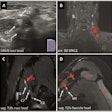

The researchers set out to test both reading methods to establish their effects on radiologist accuracy and variability. They also wanted to assess the system's performance compared with radiologists. Three radiologists -- with three, more than 10, and more than 20 years of breast ultrasound experience, respectively -- used the Koios DS software to review 500 pathology-proven breast ultrasound studies. After rendering an initial diagnosis, they were immediately presented with the software's analysis and could change their diagnosis. Four weeks later, the radiologists again read the cases, but this time concurrently with the software's analysis.